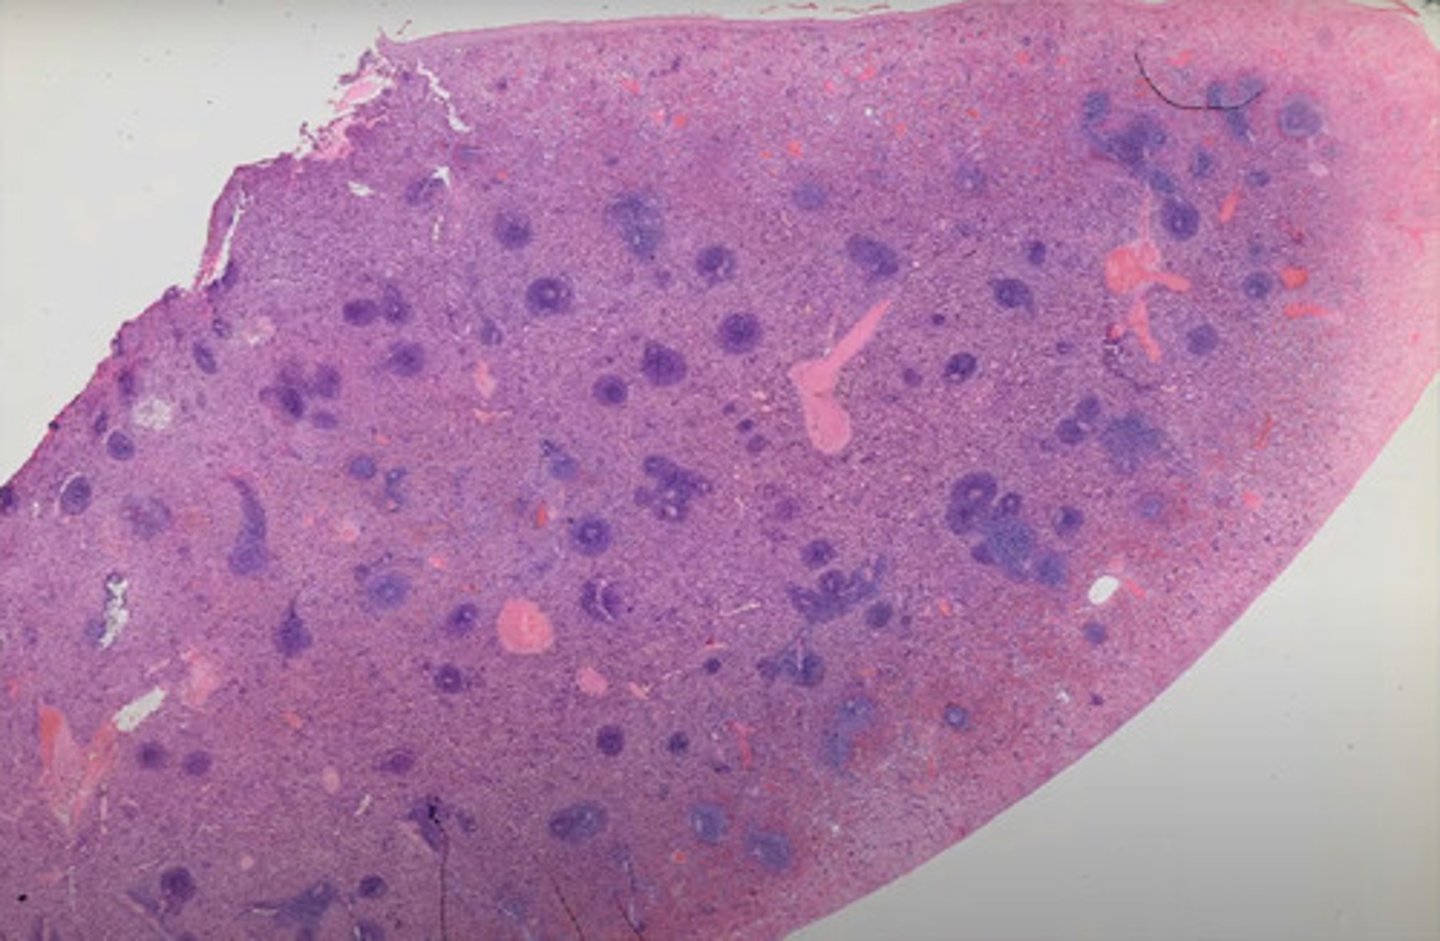

Móżdżek (H+E)

Rdzeń kręgowy (met.osmowa)